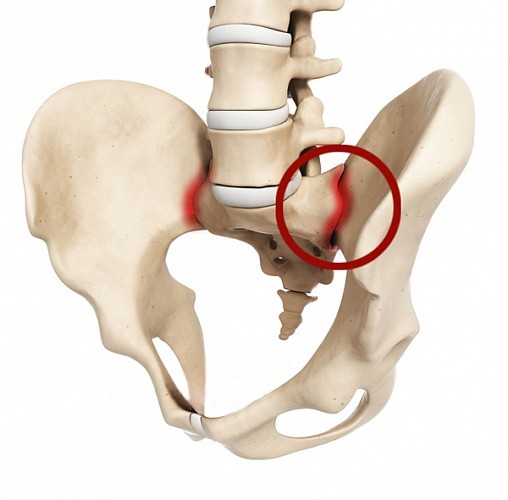

Артроз крестцово-подвздошных сочленений

Артроз считается одним из самых распространенных заболеваний суставов. Однако некоторые виды этого недуга встречаются не так часто. Например, случаи артроза крестцово-подвздошных сочленений считаются действительно редкостью. В современной клинической практике он встречается с частотой от 60 до 200 случаев на 100 тысяч населения. Это малораспространенное заболевание характеризуется как хронический дистрофический процесс. Сопровождается он длительным воспалением в крестцово-подвздошном суставе. Проявляется в виде сильных болей, которые могут быть спровоцированы большими физическими нагрузками или переохлаждениями.

Причины

Возникнуть заболевание может из-за различных факторов. Сегодня специалисты еще не смогли выявить единую причину, которая провоцирует проблему. Однако они выделяют следующие наиболее распространенные факторы, способствующие развитию артроза крестцово-подвздошных сочленений:

Какой врач лечит артроз крестцово-подвздошного сочленения?

Начинать терапию необходимо при появлении первых симптомов заболевания. Однако многие люди даже не знают, какой врач лечит артроз крестцово-подвздошного сочленения. Справиться с этой проблемой поможет невролог. Он ставит диагноз после осмотра пациента, а также опроса, в течение которого он выясняет:

Что если не лечить болезнь?

Необходимо отметить, что заболевания, которые развиваются на фоне этого недуга, достаточно опасны. Они могут стать причиной тяжелых нарушений функционирования органов малого таза. Наиболее часто заболевание в запущенной стадии вызывает нарушение подвижности позвоночника. В таком случае человек полностью теряет трудоспособность, качество его жизни значительно снижается. Если не лечить болезнь, то она может привести к инвалидизации больного.

Особенности лечения

Терапия при артрозе крестцово-подвздошных сочленений направлена в первую очередь на устранение первопричины заболевания. Исходя из сложности и распространенности недуга, врачи выбирают метод лечения. Справиться с болезнью можно как медикаментозной терапией, так и с помощью хирургического вмешательства. Последний метод используется в случаях, когда крестцово-подвздошный артроз спровоцирован инфекционными поражениями или когда он находится в запущенной стадии.